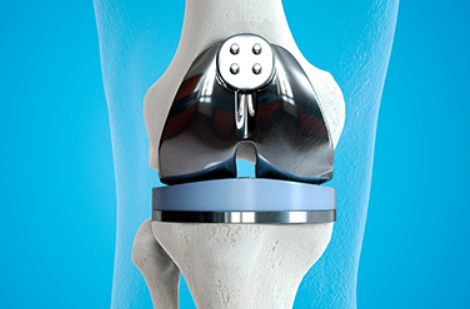

무릎 인공관절 수술은 손상된 관절을 금속이나 특수 플라스틱 재질의 인공관절로 바꾸는 수술이에요. 대표적으로 퇴행성 관절염이 심해져 약물이나 물리치료로는 더 이상 효과를 보기 어려운 경우에 시행돼요.

최근에는 로봇을 활용한 정밀한 무릎 인공관절 수술이 많이 시행되고 있어요. 3차원 데이터로 환자의 뼈 상태를 분석해 가장 이상적인 절삭 범위와 삽입 위치를 자동으로 계산해 준답니다.

정확한 수술이 가능하기 때문에 뼈나 신경, 연부 조직 손상이 적고 수술 후 회복도 빠른 편이에요. 큐비스-조인트처럼 자동화된 수술 장비도 점점 보급되고 있어요.